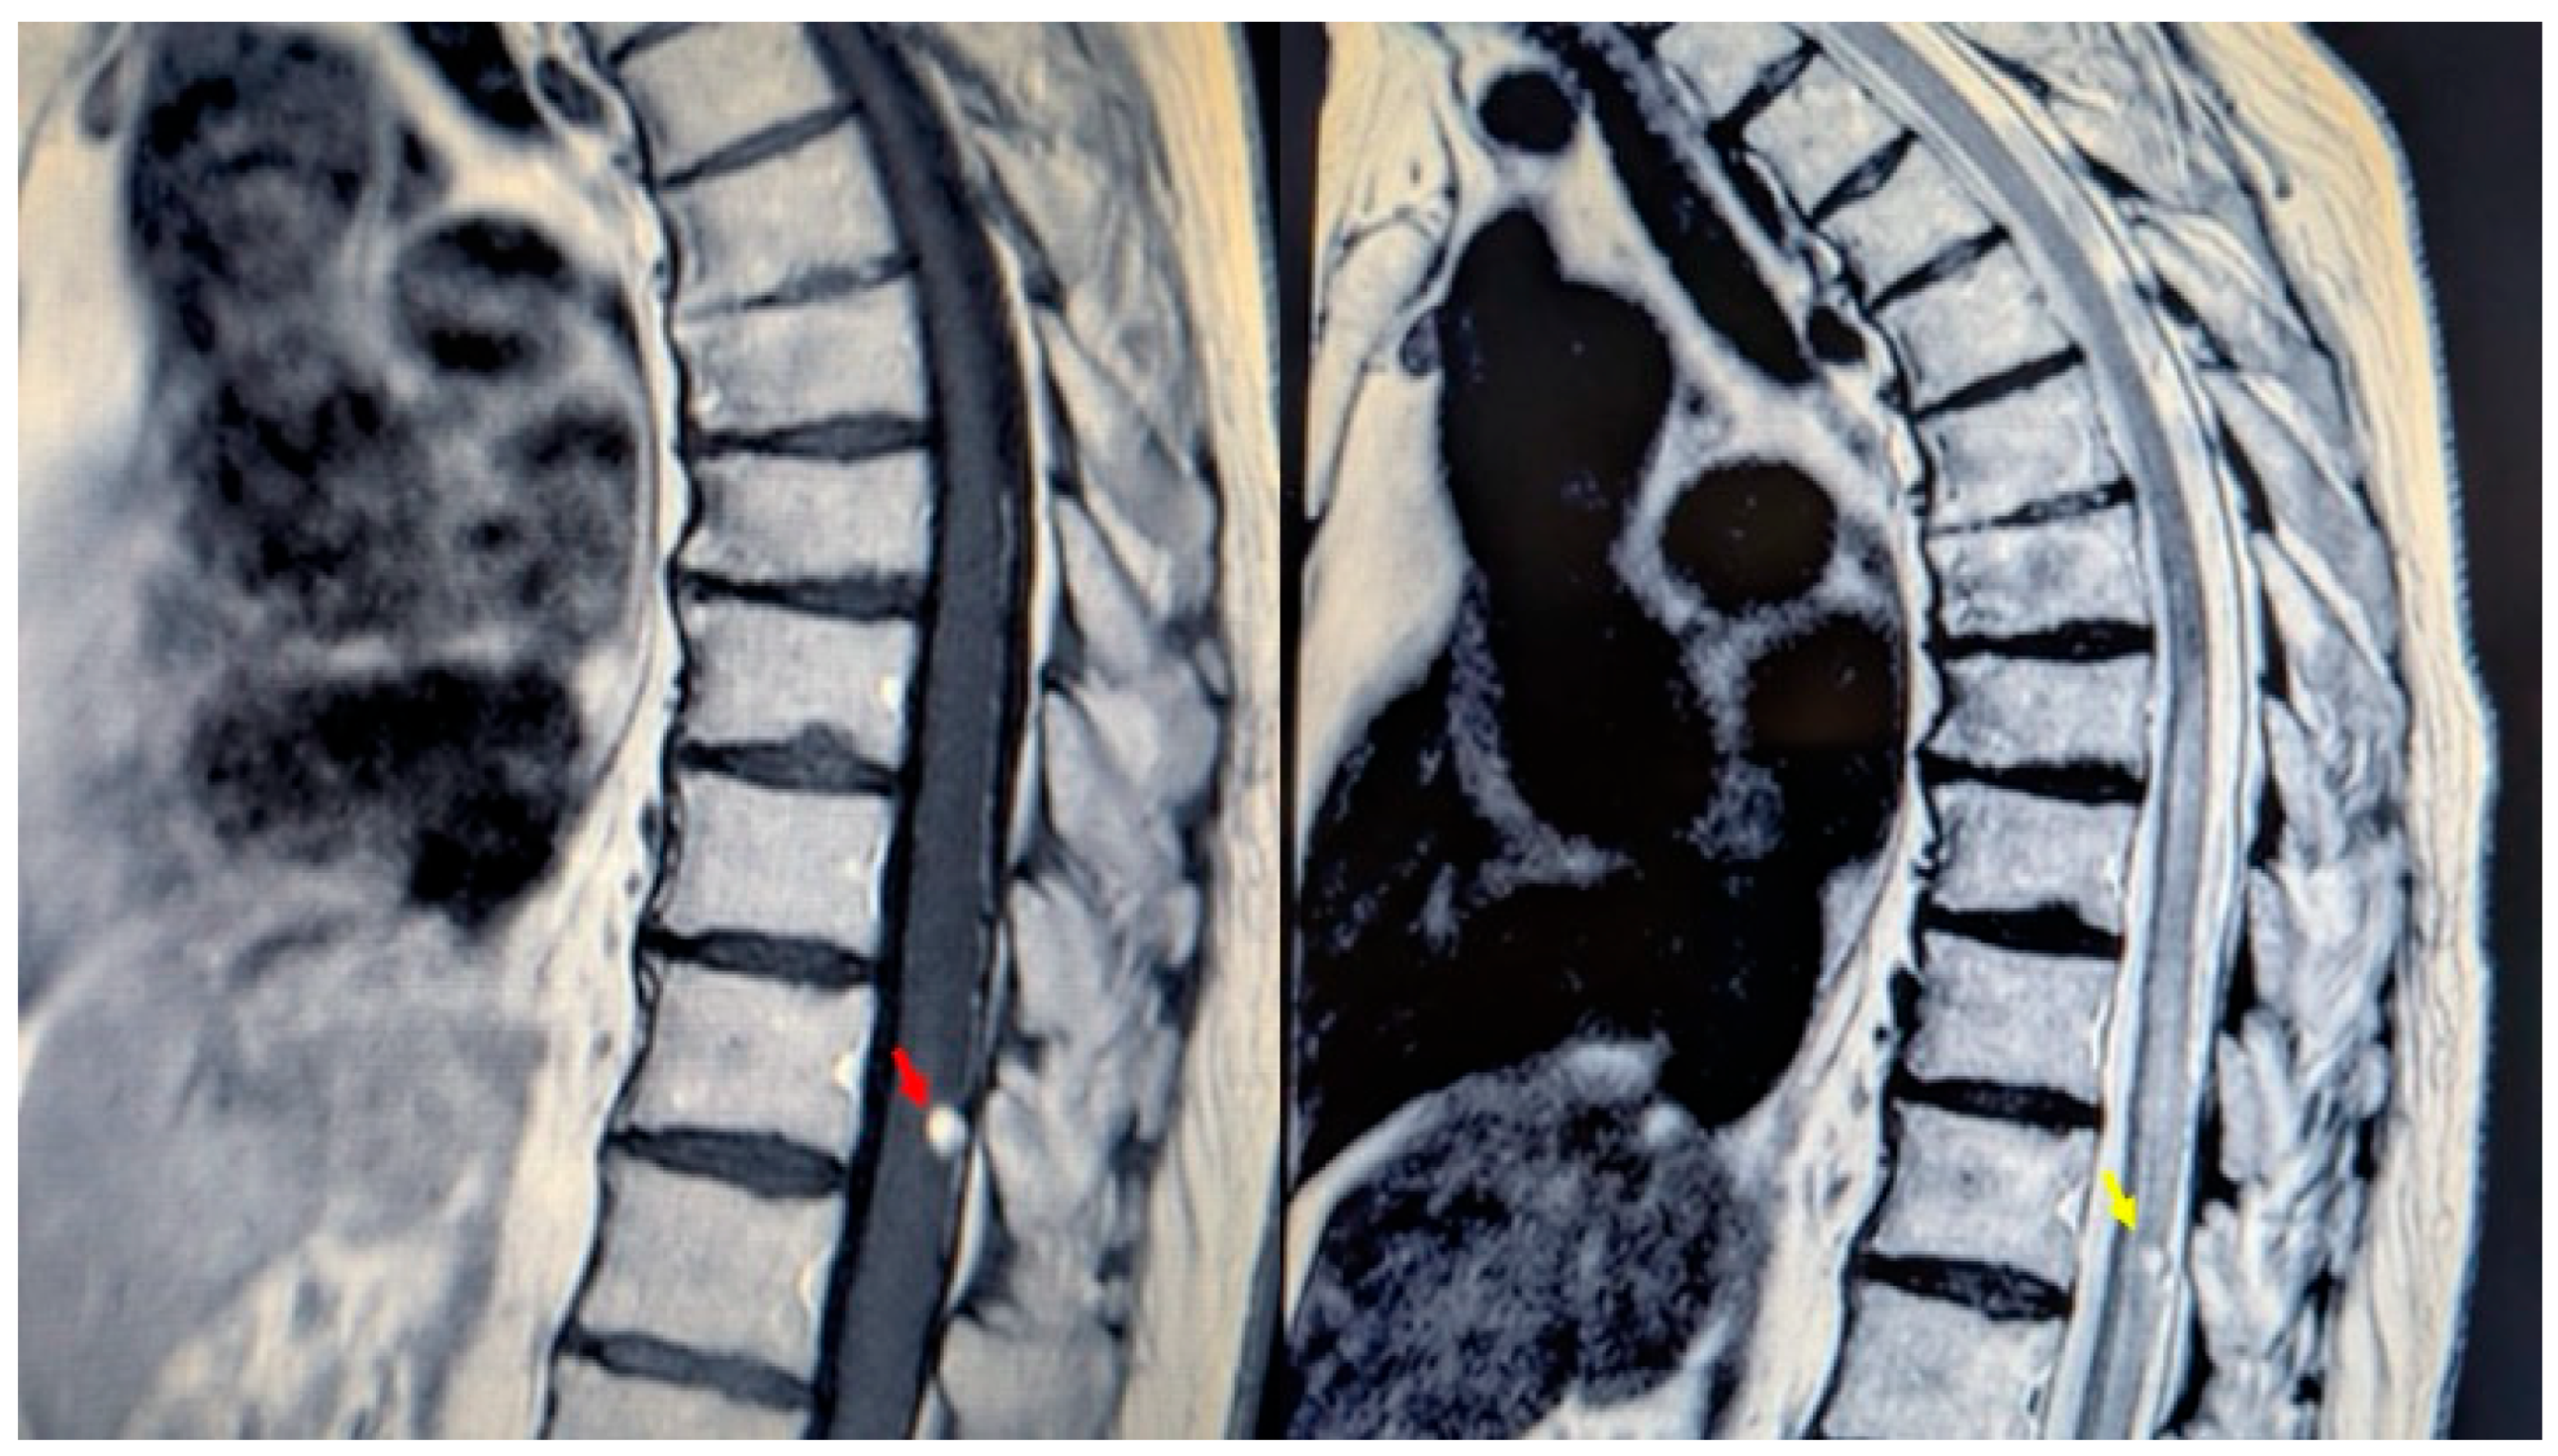

Figure 1.

MRI of the thoracic spine. Left: T1-weighted image showing the expansive lesion at the T11 level (red arrow). Right: T2-weighted image revealing the lesion with surrounding edema (yellow arrow).